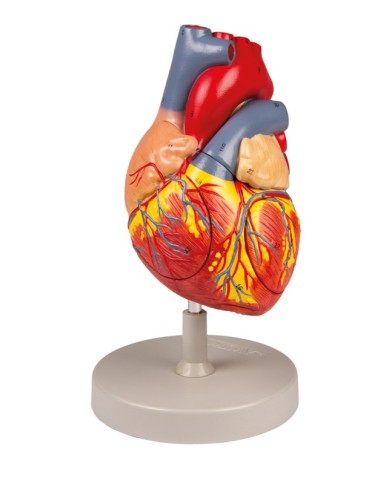

Modello di cuore di alta qualità scomponibile in 5 parti

Modello di cuore di alta qualità scomponibile in 5 parti

Modello anatomico di cuore, ingrandito 2 volte, su cavalletto

Realizzato in stampa 3D ad elevatissima risoluzione a colori.